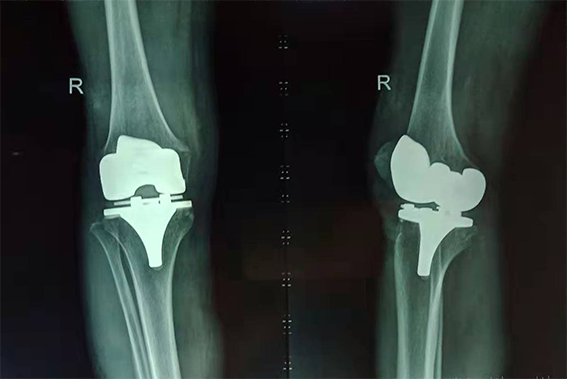

吳奶奶術(shù)后右膝X光片

“頭天做了手術(shù),第三天就能下地走路了,真是太神奇了!這給子女們減輕了不少負(fù)擔(dān)。”吳奶奶高興地說。目前她正在醫(yī)生的指導(dǎo)下,進(jìn)行康復(fù)訓(xùn)練。